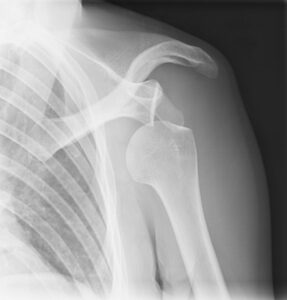

Omuz Çıkığı

Omuz ekleminin top şeklindeki üst kısmının, yuvasından (skapula) yerinden çıkması sonucu meydana gelir. Bu tür bir yaralanma, omuz ekleminin çok …